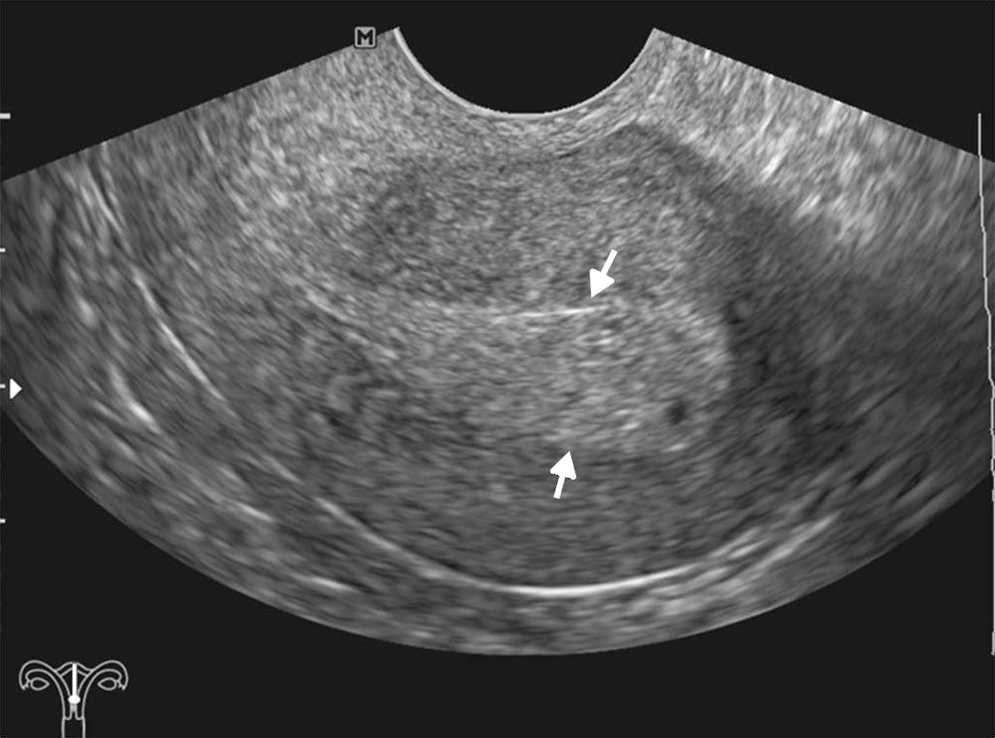

Las principales causas de esta dolencia son los quistes de ovario simples o hemorr??gicos, los embarazos ect??picos, las enfermedades inflamatorias pelvianas, las torsiones de ovario y otras patolog??as, muchas de las cuales tienen caracter??sticas ecogr??ficas propias que permiten su diagn??stico5 (figs. 1-3).

La ecograf??a determina la naturaleza s??lida o qu??stica de las masas anexiales, la presencia de septos o elementos s??lidos, y su vascularizaci??n con la exploraci??n Doppler (fig. 4). Estos hallazgos ayudan a determinar la benignidad o malignidad de la masa5,10.